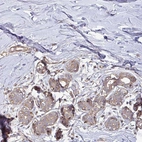

Immunohistochemical staining of human breast shows moderate cytoplasmic positivity in glandular cells.